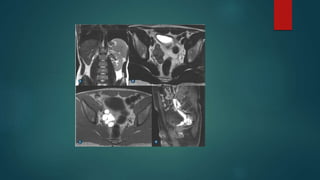

ADENOCARCINOMA

PARAGANGLIOMA

CISTOADENOCARCINOMA

INVASÃO SECUNDÁRIA TUMOR DE

PRÓSTATA